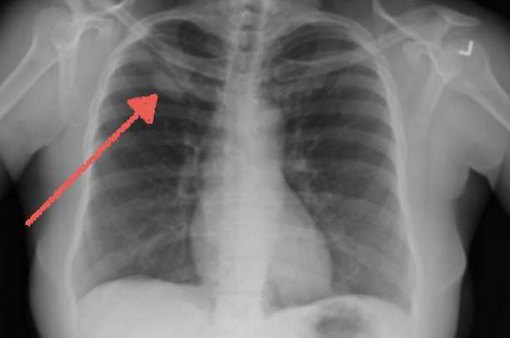

Рентгенограмма аденокарциномы лёгкого

- Визуализационных методов исследования. На рентгенограмме лёгких просматриваются периферические участки инфильтрации с признаками опухолевого роста. КТ и МРТ грудной клетки помогают уточнить локализацию новообразования, выявить метастазы в регионарных лимфатических узлах, контрлатеральном лёгком. МРТ, ПЭТ КТ и остеосцинтиграфия применяются для определения удалённых секундарных изменений.